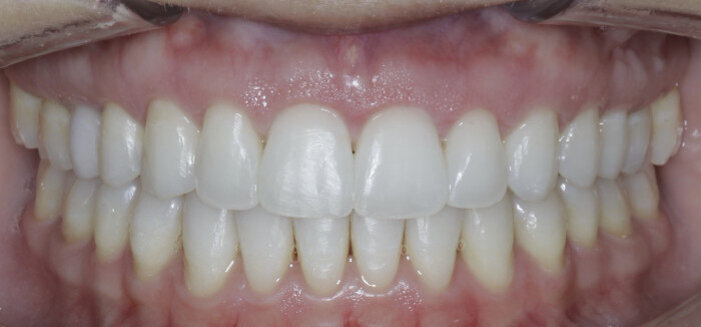

Once the intrusion has been completed, the TADs are tied to the wire and vertical elastics are used to close the bite without relapse of the intrusion. If buccal crown tip is seen, owing to the movement created by the intrusion, a power chain torquing sling is used to encourage lingual crown tipping and to prevent flaring of the incisors (Fig. 9). Once the case has been completed, the appliance is removed and a gingivectomy is performed to idealise the tissue shape and the final contours are made to the hard tissue (Figs. 10–12, end of treatment).

In some cases, intrusion may occur asymmetrically (one side faster than another, or the anterior faster than the posterior). For these occurrences, when one area has been completed with intrusion, the TAD is tied to the wire and intrusion continues in the others until all intrusion has been completed. A gingivectomy and hard-tissue contouring are completed (Figs. 27–29, end of treatment).